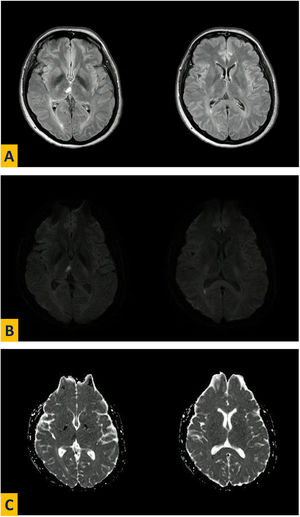

A las 24 h se realizó una resonancia magnética cerebral con evidencia de infarto isquémico talámico medial derecho y microinfarto en la pared posterior del atrio ventricular ipsolateral, que no concordaba con lateralidad del déficit, y sin evidencia de lesiones nuevas o antiguas a otro nivel consistentes con hallazgos al examen neurológico o que sugirieran lesión reperfundida en territorio vascular contralateral (fig. 1). Con el fin de identificar las vías aberrantes del TCE que aclararan síntomas ipsolaterales, se solicitó una tractografía con tensor de difusión, en la cual se evidenció ausencia de decusación del TCE como variación anatómica (fig. 2), lo que explica la presencia de síntomas ipsolaterales.